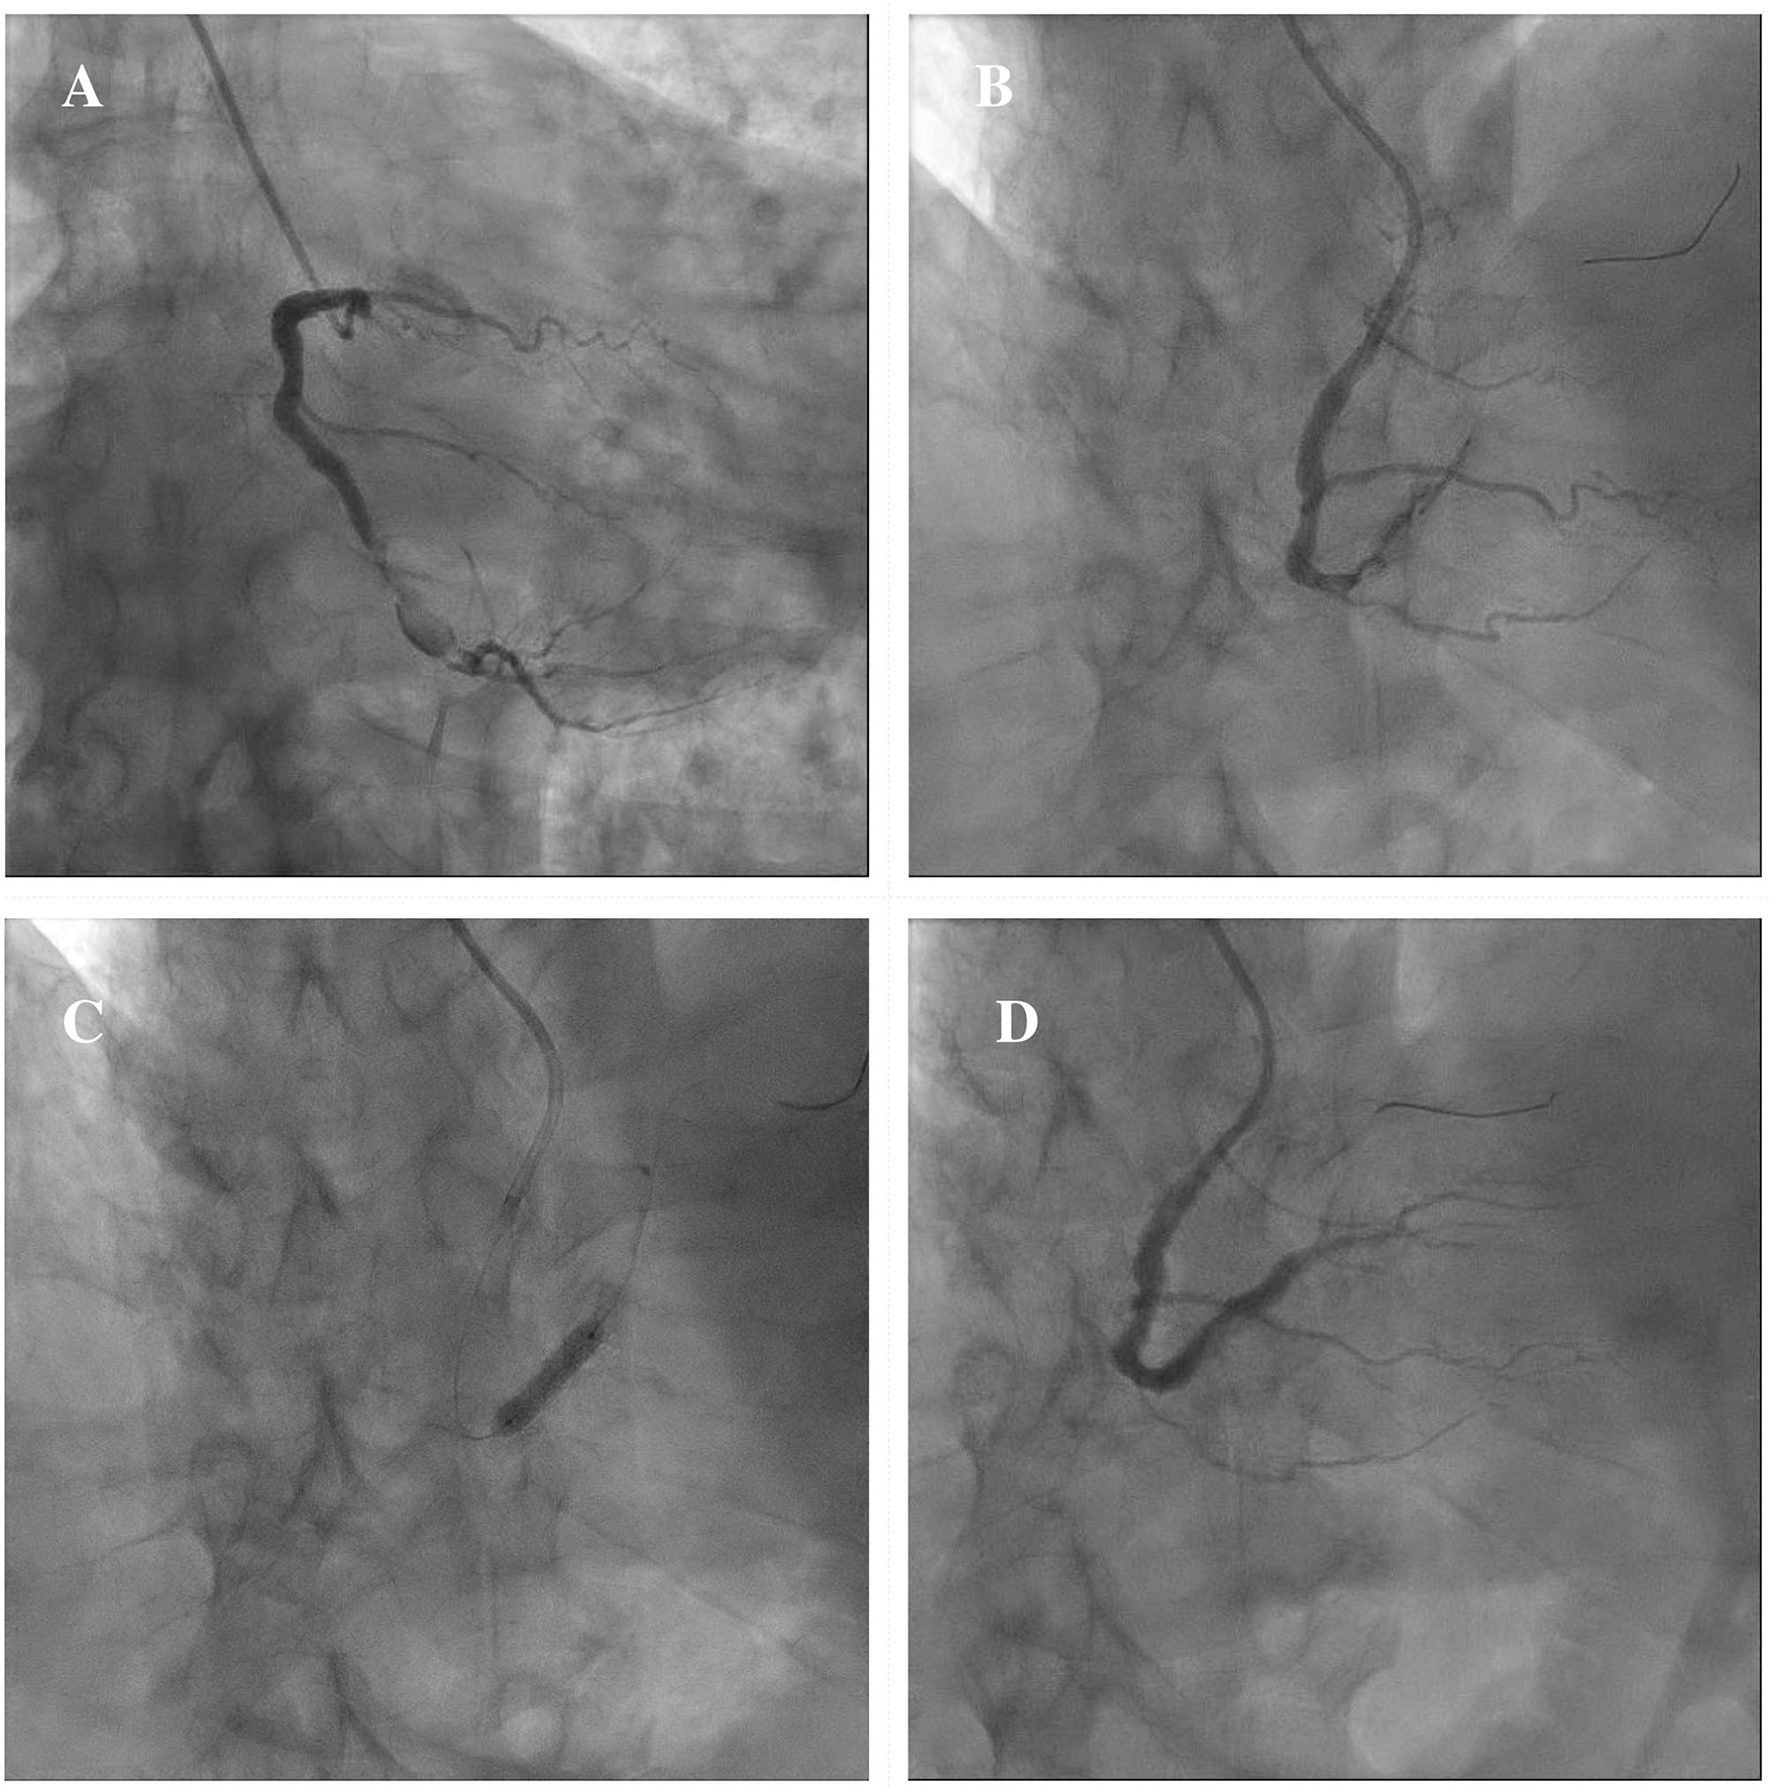

In consideration of these technical challenges, if PCI is clinically indicated, different percutaneous techniques should be adapted to the anatomical scenario. Exclusion with covered stents might be indicated in saccular CAAs or small pseudoaneurysms not involving major side branches (11). Figure 6 illustrates a case showing the successful covered stent exclusion of a saccular CAA in the distal RCA with high thrombus burden. Different covered stents are currently available, but GRAFTMASTER (Abbott Vascular, Santa Clara, California) and PK Papyrus (Biotronik, Berlin, Germany) are the most frequently used. The GRAFTMASTER is constructed using a sandwich technique, with an ultra-thin layer of expandable polytetrafluoroethylene (PTFE) placed between 2 stainless steel stents, which are then pre-mounted on a balloon catheter delivery system. The stent can be used from diameters ranging from 2.8 to 5.5 mm and can be delivered through a 6 or 7 Fr guiding catheter, depending on the size of the device. PK Papyrus is a new-generation cobalt chromium single covered stent. Because of its advanced single stent design, it has greater bending flexibility and smaller crossing profile compared to GRAFTMASTER and can be delivered through a 5 or 6 Fr guiding catheter. For diameters from 5.5 mm to 10 mm the Atrium iCAST balloon expandable covered stent (MAQUET, Wayne, New Jersey) can be used, but an 8 or 9 Fr guiding catheter is needed. However, the use of covered stents is limited by several technical issues: the stiffness of the device, the poor deliverability and the need for large sheaths and guiding catheters are associated with a higher risk of procedural complications, especially in severely tortuous and calcified vessels. Moreover, the risk of side branch loss represents one the major limitation of covered stents. Different techniques have been described to avoid major side branches loss during covered stent implantation. GRAFTMASTER is a one-size stent mounted on different sized balloons and therefore its skirt can be shortened by ~3 mm with high-pressure post-dilatation using large non-compliant balloons: this technique allows to fully cover short CAAs, without landing at the level of major side branches (91, 92). Recently Davies et al. described a novel technique to treat large CAAs involving bifurcations with large side branches: first, a PK Papyrus is implanted from the proximal to the distal main vessel; second, a stiff guidewire with high tip load supported by a microcatheter is used to puncture across covered stent into the side branch; third, the microcatheter is advanced through the PK Papyrus to enlarge the opening and is used to exchange the stiff wire with a regular workhorse; Excimer laser atherectomy is then performed to ablate the polyurethane membrane of the covered stent at the level of the ostium of the side branch; finally, the PK Papyrus stent strut can be dilated with single balloon and double kissing balloon inflations (93). A similar fenestration technique of PK Papyrus without the use of excimer laser, has been carried out to gain access to the LAD in a case of covered stent implantation from the LM to the LCx for a perforation of the ostial LCx (94). However, these cases remain anecdotal and are not supported by data from observational studies; therefore, similar techniques should be limited to bail-out situations in specific anatomical settings and should be performed by experienced operators in complex PCI. Furthermore, in large CAAs involving major bifurcations, not suitable for percutaneous treatment, CABG remains a valuable option.

Figure 6

Example of exclusion of a saccular CAA in the distal RCA with high thrombus burden by means of covered stent implantation. Severe ISR of a previously implanted DES in the distal segment of the RCA continuing in a saccular CAA with high thrombus burden (A). A 3.5 × 15 mm PK Papyrus covered stent is advanced to precisely seal the inlet and outlet of the CAA (B). A DES Synergy (Boston Scientific, Marlborough, Massachusetts) 4 x 24 mm is then implanted proximally to the covered stent to treat the severe ISR (C). Final result showing the exclusion of the saccular CAA (D). CAA, coronary artery aneurysm; DES, drug-eluting stent; ISR, in-stent restenosis; RCA, right coronary artery.